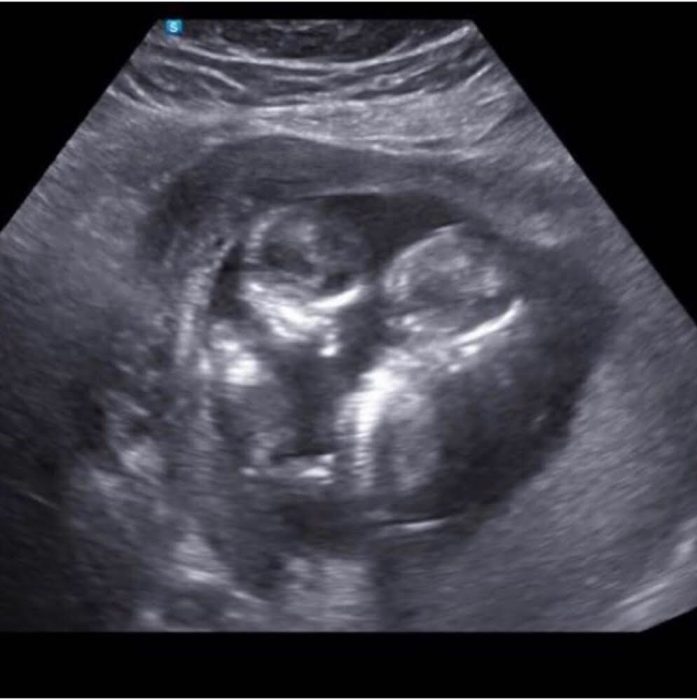

“I suggested that she should go to a pregnancy center and that she could get help there,” said Grace. “She went and while she was there she had an ultrasound. She is now 4 or 5 months pregnant with twin girls and she’s going to keep them!”

The new mother has chosen names for her daughters and is looking forward to their birth.